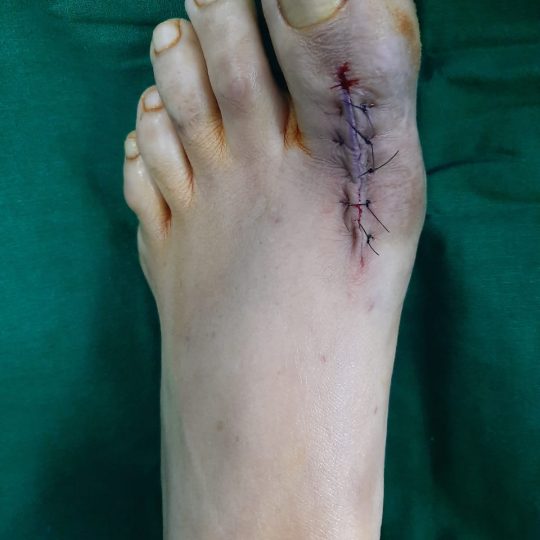

Patient’s Successfully Treated with Diabetic Foot Problems